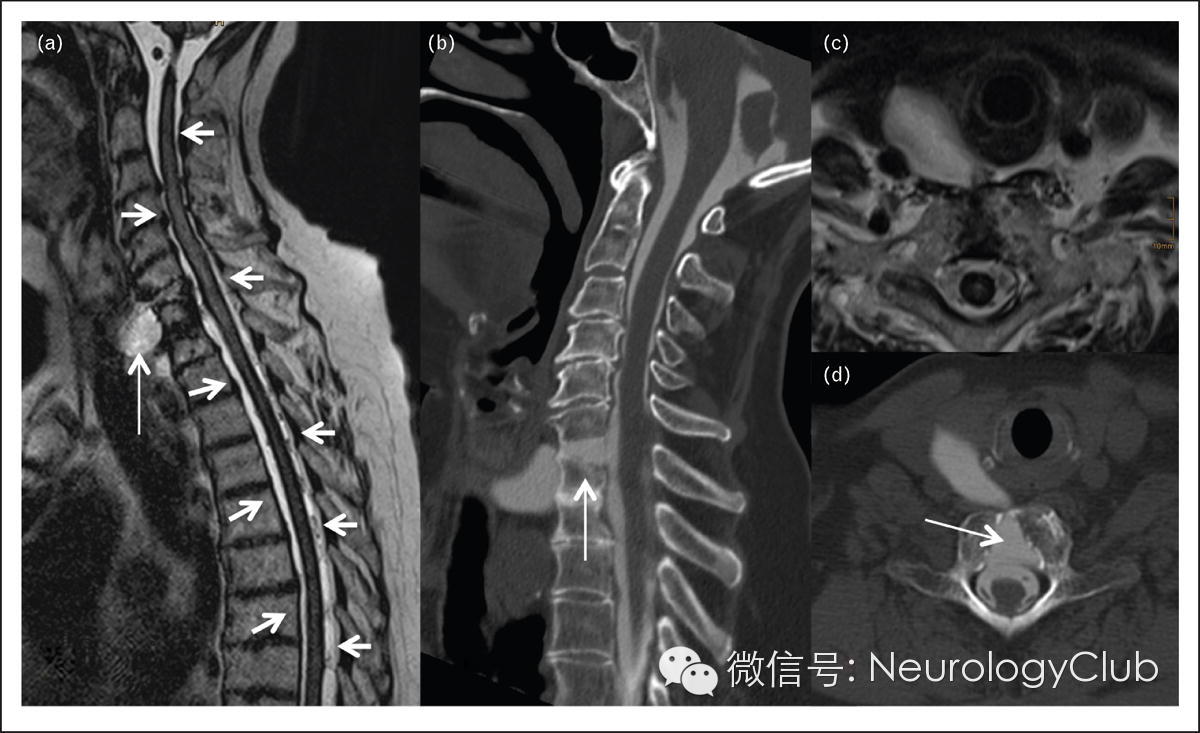

图3 低颅压伴软脑膜含铁血黄素沉积

54岁女性,诉体位性头痛,共济失调,认知功能下降。矢状位(图a)和轴位(图c)T2快速自旋回波图像提示脊髓表面有含铁血黄素沉着(短箭,图a,c),并发现C7椎体的右前外侧方有一个充满液体的结构(箭,图a)。CT脊髓造影(箭,图b,d)显示蛛网膜下腔和椎前囊有广泛的交通。20年前患者曾行C6/C7椎体融合术。大多数材料已被吸收,残存的材料在交通区的边缘仍然可见。